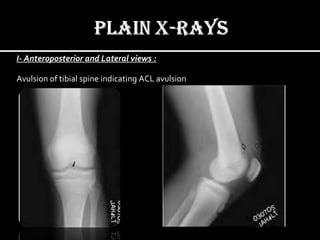

I- Anteroposterior and Lateral views :

Avulsion of tibial spine indicating ACL avulsion